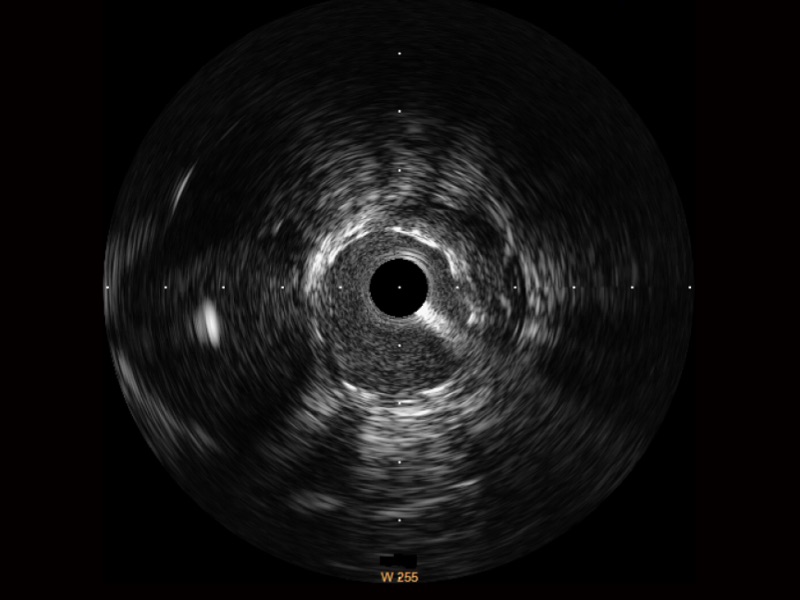

一鍵智能描跡,自動(dòng)測(cè)量斑塊負(fù)荷、面積狹窄率等指標(biāo),準(zhǔn)確率高于90%